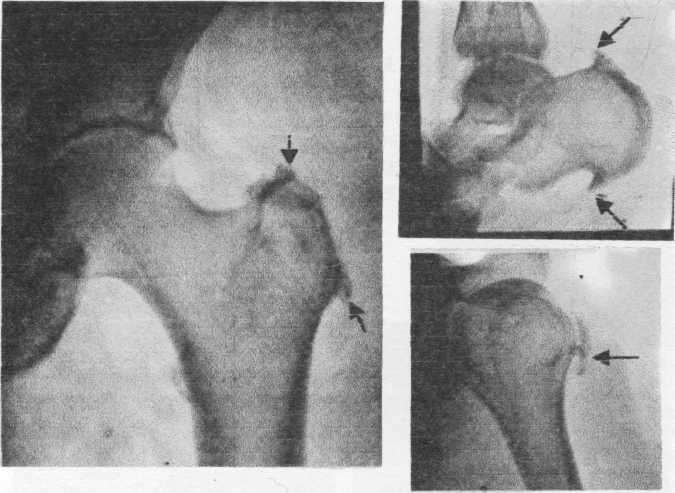

Здоровье суставов: Трохантерит и его влияние на мышцы